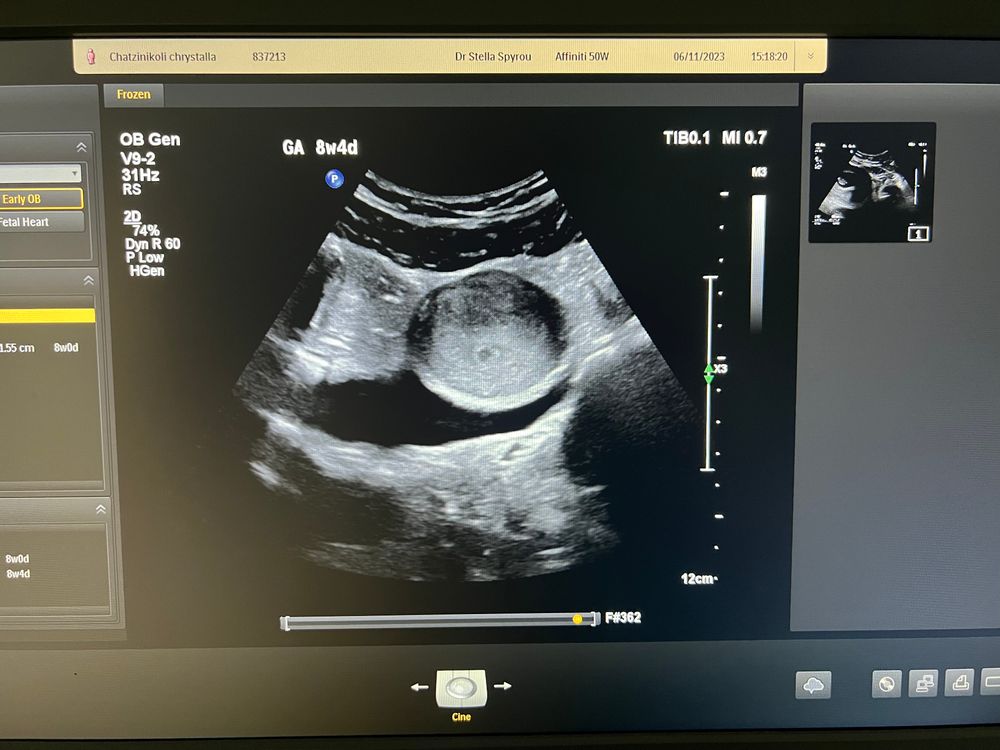

Первое узи

сегодня был прием у гинеколога и первое узи, на котором увидели нашу точечку😍

Я немного в смешанных чувствах после приема…Я на Кипре. УЗИ было через животик, это единственный кадр, который показали. Я понимаю, что срок совсем маленький и смотреть особо нечего, но ожидала более детальной информации. Мне не дали никакого заключения, не замеряли никакие размеры, никаких комментариев по поводу эндометрия. Ну и собственно никакого осмотра не было, только узи на минуточку и всё, сказали что беременность в матке. Никаких анализов не назначали. Никаких витаминов для беременных, никаких рекомендаций по питанию и образу жизни или что-то типо того.